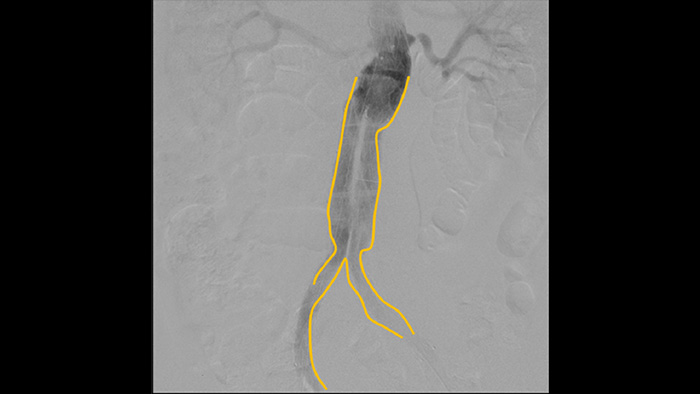

Digital subtraction angiography (DSA) is used in interventional vascular procedures to clearly visualise blood vessels by removing structures that can obscure vessel visibility. Roadmap fluoroscopy overlays a previously acquired subtracted contrast image on the live fluoroscopy, allowing you to track a device without reinjecting contrast.

Use the Outlining tool to easily mark a bifurcation or side branches by simply drawing on the monitor of the Mobile Viewing Station with your finger or an externally connected mouse.

Enhance visibility of tortuous vasculature with Iodine and CO2 contrast medium options. Easily control injections at table side. For patients with renal failure, you can use the CO2 option to easily visualise small vessels without using iodine contrast.